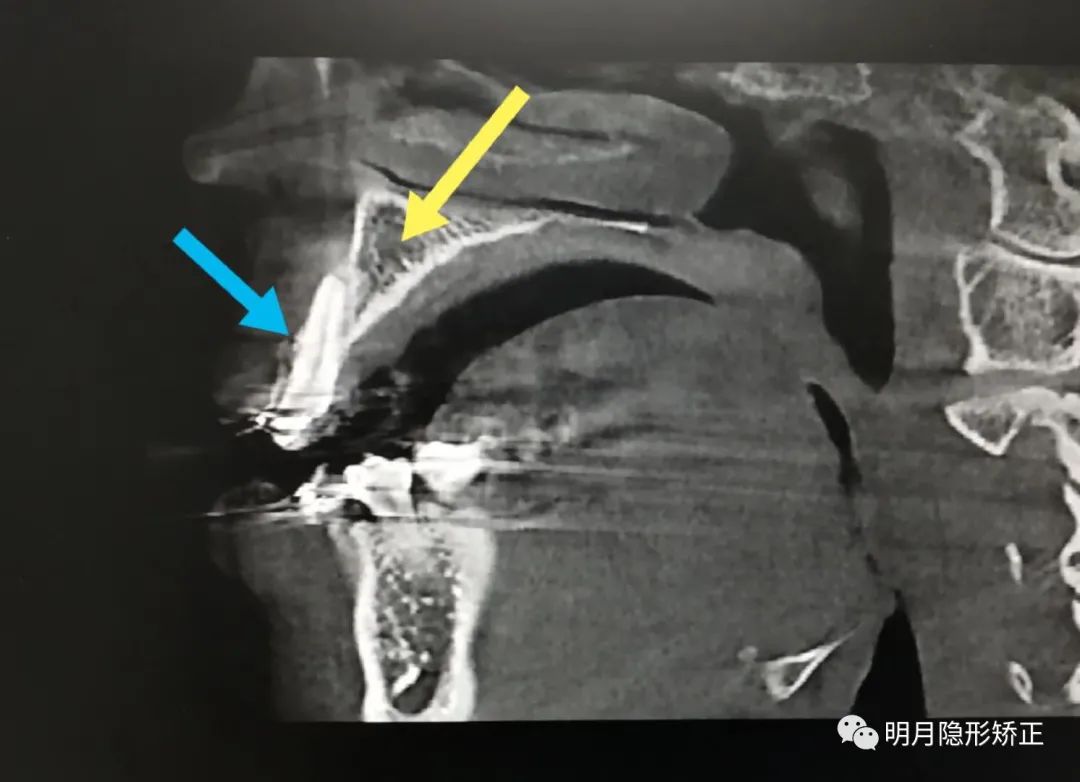

我懷疑牙根已經有問題,於是給她拍一張口腔CT。

果然,上頜兩顆虎牙已經被拉出了牙槽骨之外再加力牽引,恐怕會被拉脫出來……